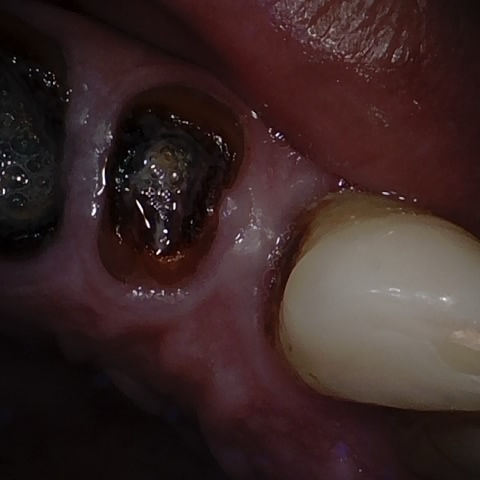

Annotated as "Good"